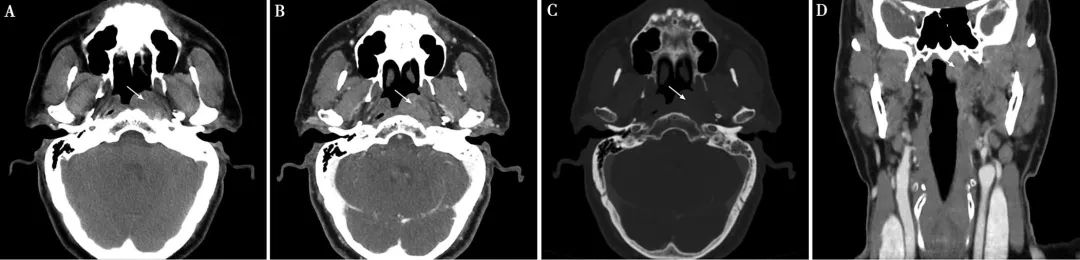

CT表現:鼻咽癌局限在黏膜間隙時(shí),CT表現爲鼻咽腔兩(liǎng)側不對(duì)稱,局部黏膜增厚,一側咽隐窩變淺或消失,腭帆提肌、腭帆張肌腫脹,脂肪間隙消失。可引起(qǐ)周圍結構的侵犯:向(xiàng)前侵犯鼻腔,達翼腭窩,向(xiàng)兩(liǎng)側侵犯咽旁間隙,向(xiàng)後(hòu)侵犯咽後(hòu)間隙以及椎前肌,向(xiàng)下侵犯口咽軟腭和扁桃體,向(xiàng)上侵犯斜坡及顱底骨質,通過(guò)顱底孔道(dào)進(jìn)入顱内。鼻咽癌常并發(fā)頸部淋巴結腫大。CT增強掃描,腫塊輕度強化,邊界不清(下圖)。

▲鼻咽癌CT表現

鼻咽左側頂後(hòu)壁及左側壁腫物,大小約1.8cm×2.7cm,呈中等強化,左側咽隐窩消失。腫物局限于鼻咽腔,未侵犯咽旁間隙。顱底未見骨質破壞。